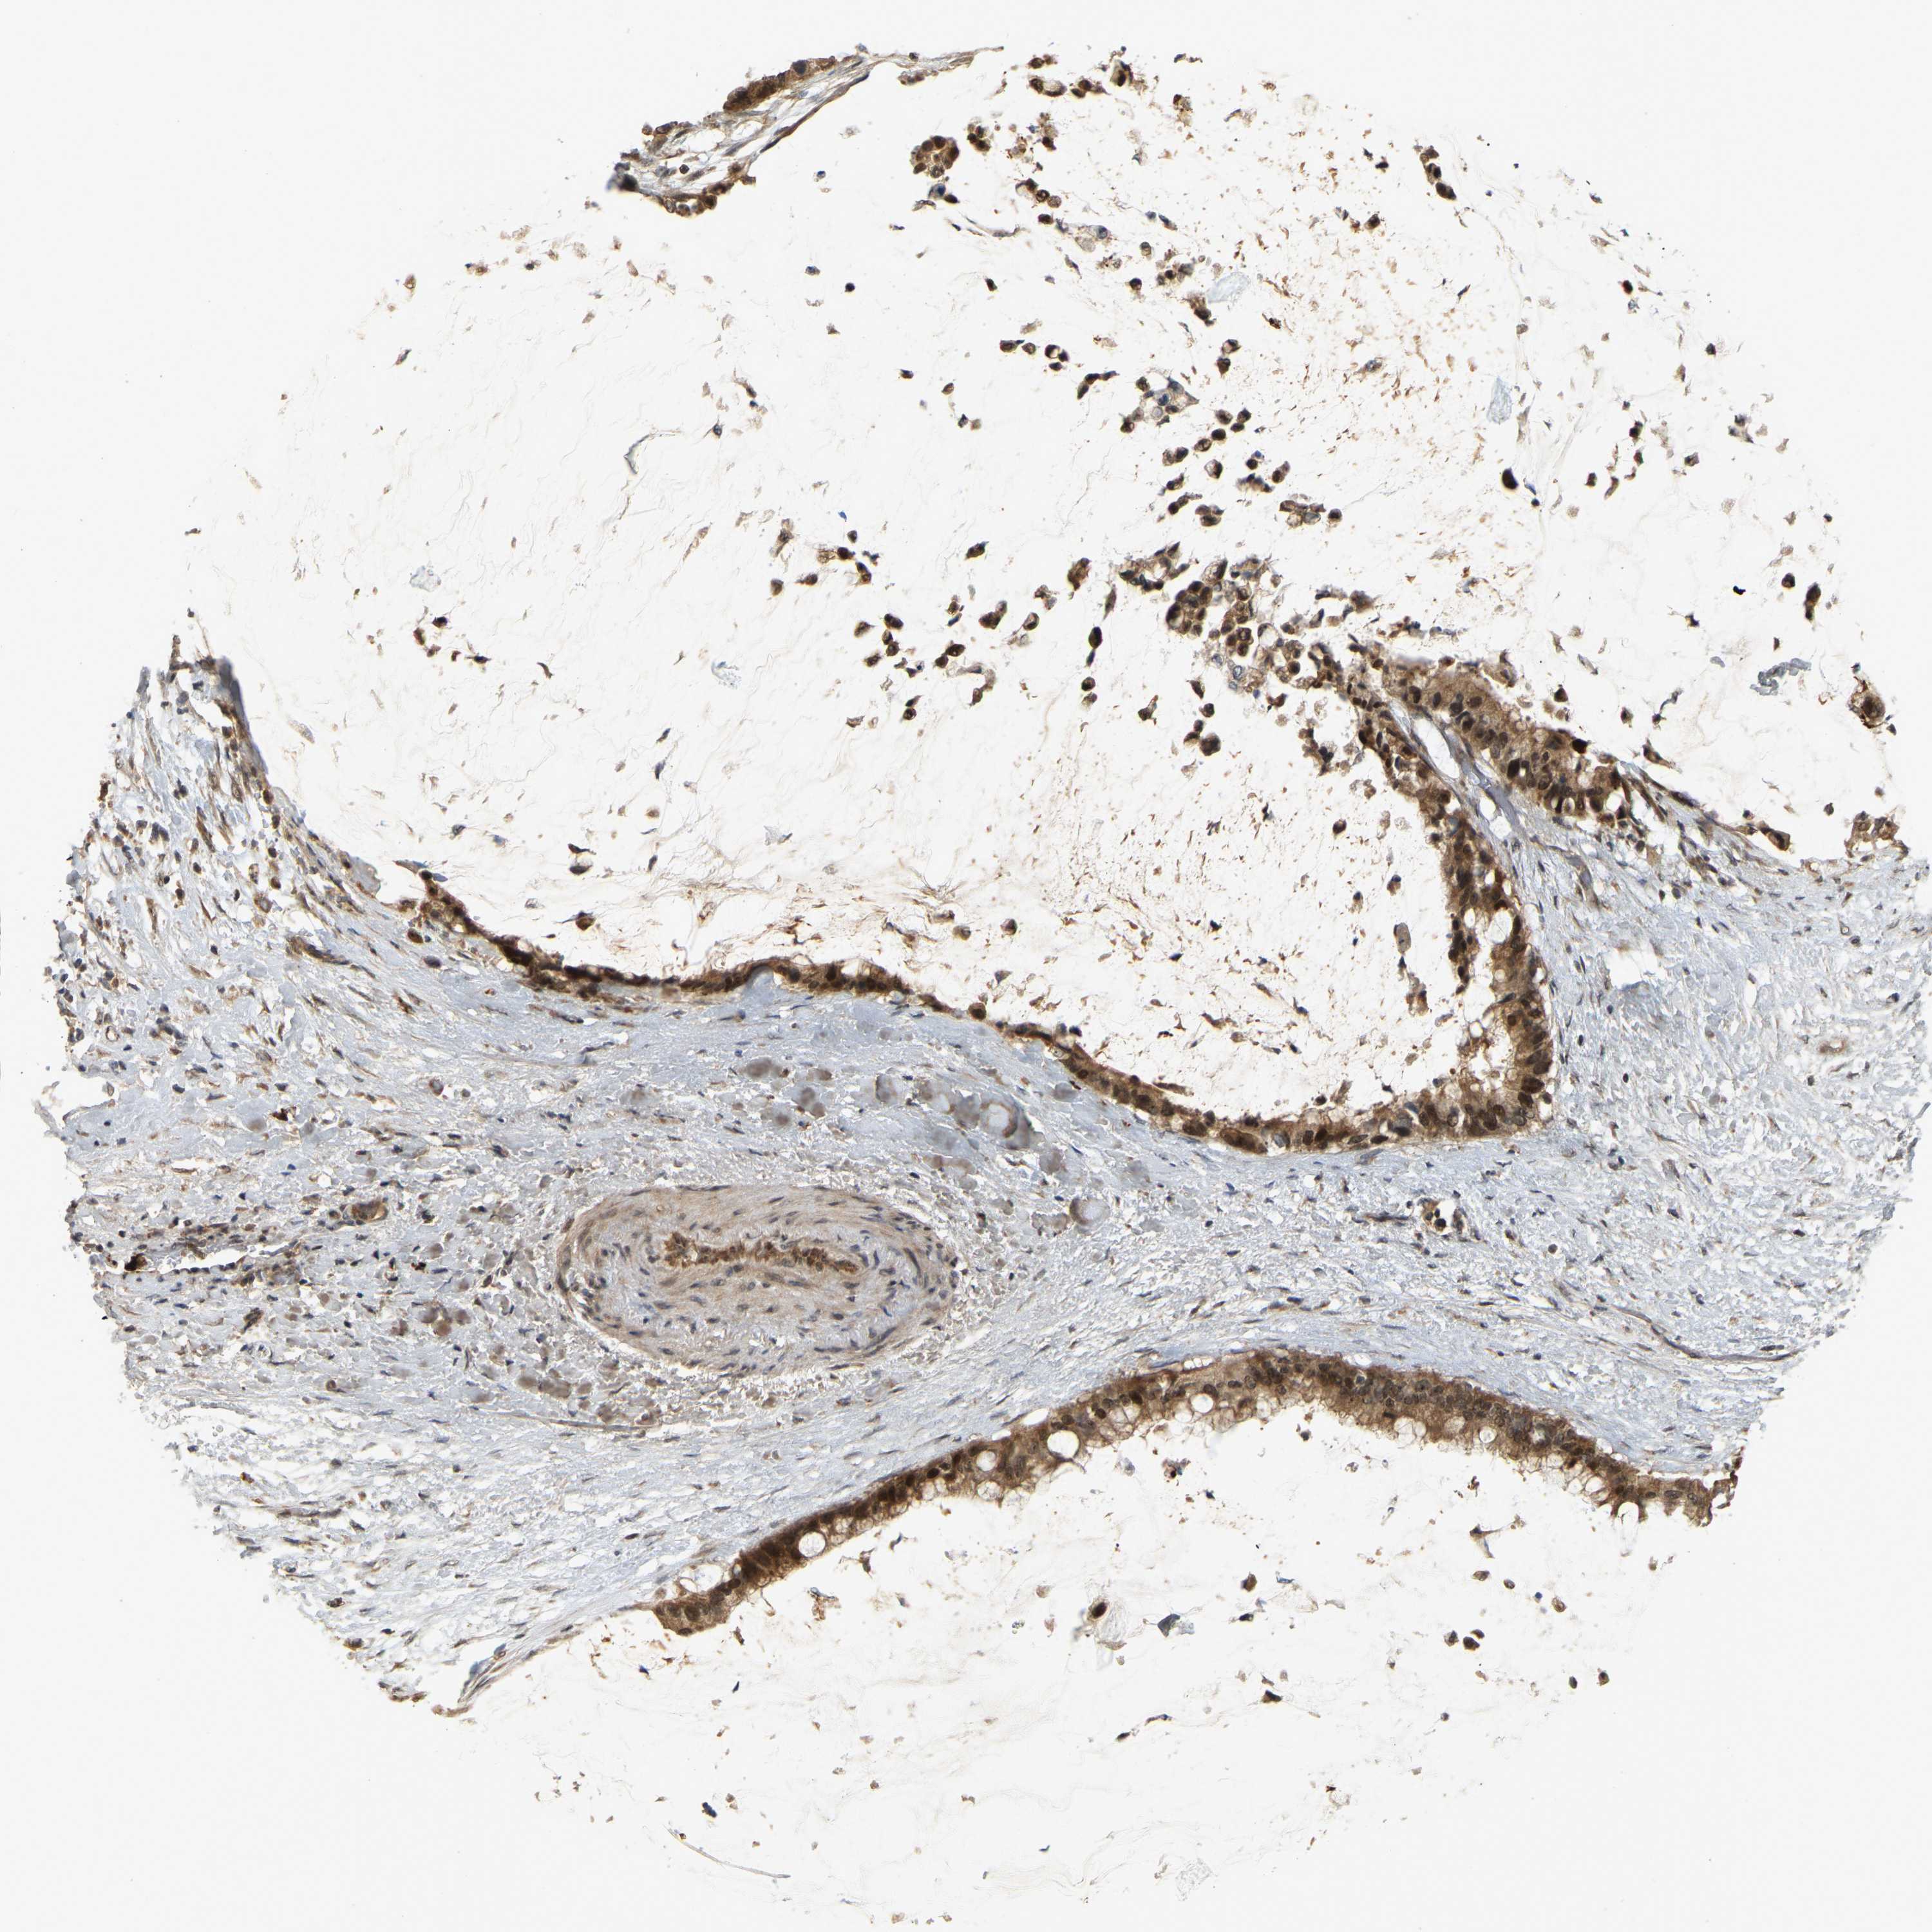

PANCREATIC CANCER - Protein expressioni

A mouse-over function shows sample information and annotation data. Click on an image to view it in a full screen mode. Samples can be filtered based on level of antibody staining by selecting one or several of the following categories: high, medium, low and not detected. The assay and annotation is described here.

Note that samples used for immunohistochemistry by the Human Protein Atlas do not correspond to samples in the TCGA dataset.

Antibody stainingi

Antibody staining in the annotated cell types in the current human tissue is reported as not detected, low, medium, or high, based on conventional immunohistochemistry profiling in selected tissues. This score is based on the combination of the staining intensity and fraction of stained cells.

Each image is clickable and will lead to virtual microscopy that enables deeper exploration of all samples and also displays staining intensity scores, fraction scores and subcellular localization as well as patient and tissue information for each sample.

Antibody HPA023378

Antibody CAB019269

Staining

High

Medium

Low

Not detected

Intensity

Strong

Moderate

Weak

Negative

Quantity

>75%

75%-25%

<25%

None

Location

Nuclear

Cytoplasmic/membranous

Cytoplasmic/membranous,nuclear

Adenocarcinoma, NOS

Adenocarcinoma, metastatic, NOS